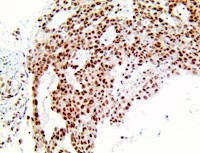

MGMT is a house-keeping gene expressed in all tissues, and its promoter methylation and resulting down-regulation of the AGT protein varies among tumor types. The MGMT promoter contains many regulatory domains, and methylation can help decrease protein expression and therefore resistance to drugs, improving effectiveness of alkylating treatments.

High MGMT antibody expression has been reported in Glioma, Myeloma, Melanoma, Colon and Pancreatic Cancers, where inhibition or down-regulation make alkylating drug treatments more effective. MGMT expression is lost in some cancer types such as Lymphomas, Non-Small Cell Lung Cancer, Astrocyte Tumors, Breast, and Prostate Cancer, where it may fail to prevent mutations. A study detected protein expression of MGMT by IHC and MGMT promoter methylation detected by methylation-specific polymerase chain reaction (MSP) were performed in a series of newly diagnosed Glioblastomas and found that the MGMT status detected by either IHC or MSP was significantly correlated with the treatment response and survival of Glioblastoma patients. MGMT methylation is frequently observed in sporadic colorectal cancer and was recently correlated with the C>T allele at SNP rs16906252, within the transcriptional enhancer element of the promoter. MGMT methylation has also been associated with KRAS mutations, particularly G>A transitions. Another study address the association between sequence variants within the MGMT (O(6)-methylguanine-DNA methyltransferase) promoter-enhancer region and methylation of MGMT in premalignant lesions from smokers and lung adenocarcinomas, their biological effects on gene regulation, and targeting MGMT for therapy and found strong evidence that the A allele of a MGMT promoter-enhancer SNP is a key determinant for MGMT methylation in lung carcinogenesis. Moreover, TMZ treatment may benefit a subset of lung cancer patients methylated for MGMT.